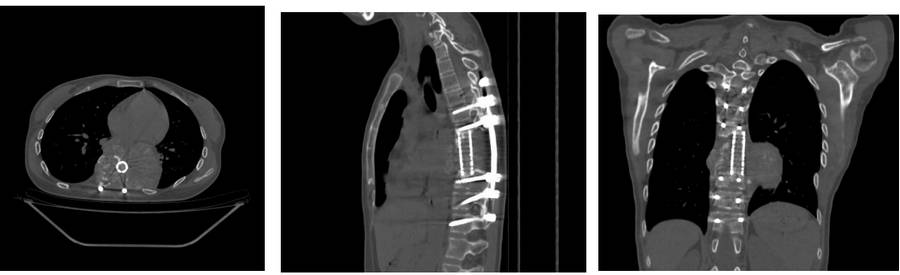

Ameliyat öncesi: Tomografi kesitlerinde daha önce uygulanan kafes ve enstrümentasyon ile birlikte tümör nüksü görülmekte